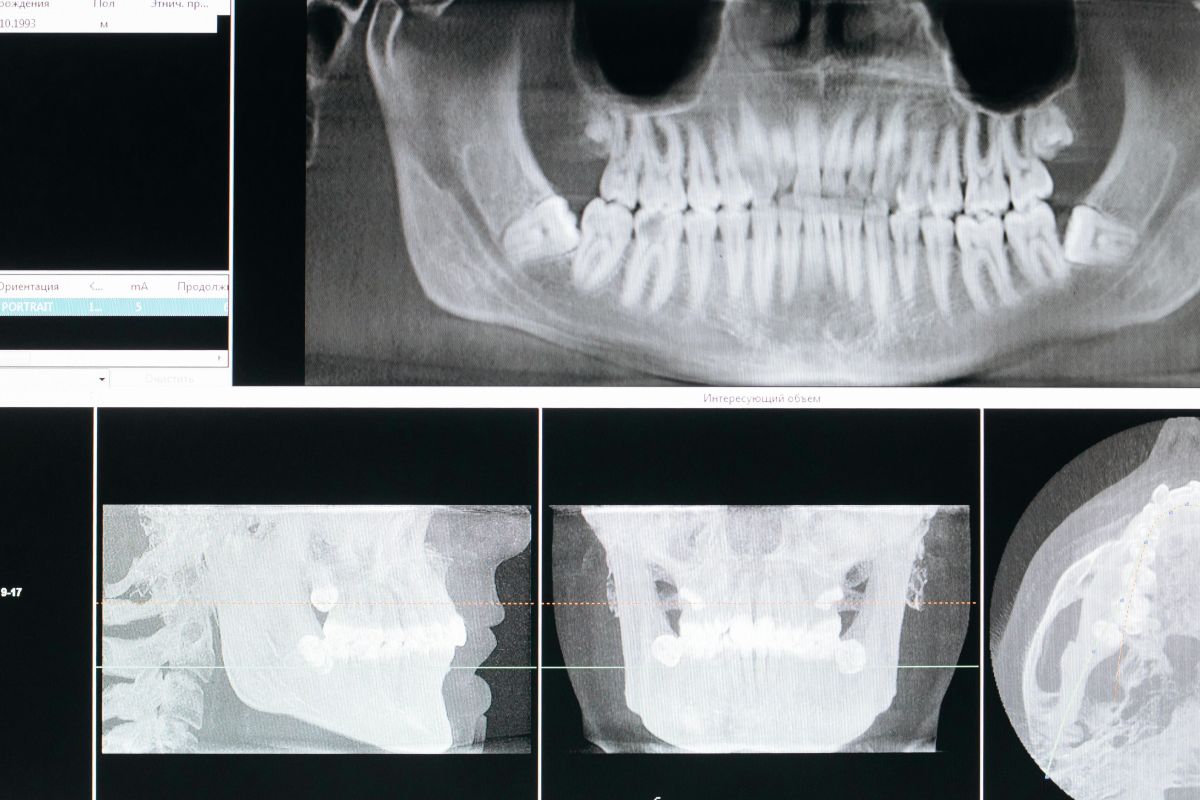

Para fundamentar una reclamación por errores en prótesis dentales, la evidencia debe ser sólida y organizada. Empiece por solicitar copia íntegra de su historia clínica: informes, radiografías (periapicales, panorámicas o CBCT), fotografías intra y extraorales, modelos y registros de mordida, órdenes al laboratorio y protocolos de cementado. Conserve facturas, presupuestos, presupuestos modificados y cualquier comunicación escrita (emails, mensajes) donde consten incidencias o quejas.

Las fotografías con separadores y espejo permiten documentar lesiones en mucosa, márgenes desadaptados, espacios negros, fracturas o desgastes anómalos. Las radiografías ayudan a evaluar la adaptación marginal, la altura ósea alrededor de implantes, la angulación de pilares y la existencia de sobrecontorneados que favorecen la inflamación. Es útil complementar con registros oclusales en papel de articular y capturas de contactos en céntrica y excursiones.

- Radiografías, CBCT y fotos clínicas de calidad.

En estos escenarios, la documentación es aún más relevante: análisis fotográfico de sonrisa, perfiles de emergencia, torque de tornillos registrado, pruebas de pasividad (test del tornillo único), y protocolos de mantenimiento. Si se produce un fracaso, la pericial evaluará si el plan era realista, si se informó de alternativas (p. ej., injertos, elevación de seno, ortodoncia previa) y si los controles se realizaron con la periodicidad adecuada.